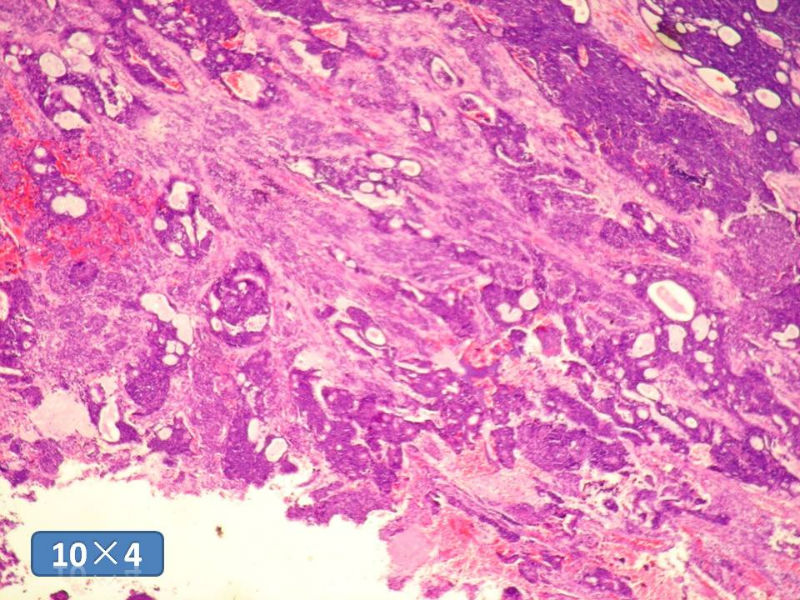

男性,49岁,间断左鼻腔出血3个月。

标签:是嗅母么?

1)嗅神经母细胞瘤?

2)腺肌上皮癌?

3)肌上皮癌?

4)神经内分泌癌?

5)腺样囊性癌?

6)其他?

腺肌上皮癌

感觉要排除畸胎癌肉瘤。

间质为恶性梭形细胞成分,其间感觉是腺体,两种成分密切相关....

免疫组化S-100的阳性区域方式...嗅母可能性大。

支持嗅神经母细胞瘤(伴有腺体分化)

嗅神经母细胞瘤

有上皮和间叶2种结构,畸胎性癌肉瘤是要考虑一下的吧!